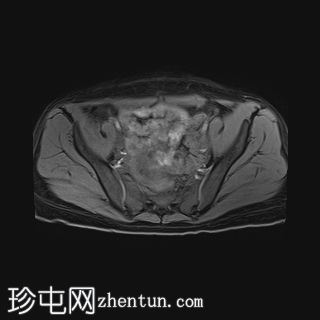

T2加权像

轴位

3.jpg

左侧卵巢增大、水肿,位置异常,卵泡呈周边排列

左侧卵巢血管扭转,呈漩涡征

左侧卵巢实质出血性改变

可见左侧卵巢少量囊肿,内含血信号

未见明显强化软组织肿块

上述左侧卵巢增大、水肿、位置异常、卵泡呈周边排列、实质出血的特征提示卵巢扭转伴出血。梗死。

患者被转诊至妇科医生处,并紧急行输卵管卵巢切除术。病理检查显示广泛的出血性梗死,卵巢包膜下仅残留薄薄一层完整组织。未发现恶性肿瘤